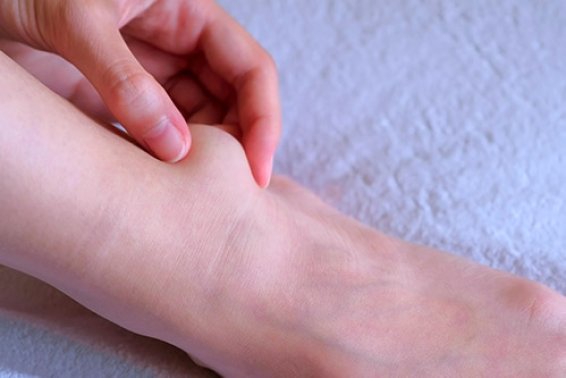

Ganglion cysts: causes symptoms and relief strategies

Ganglion cysts are fluid-filled sacs that most commonly appear on the back of your wrist or hand. However, they can also ...